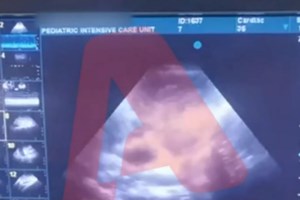

Κατά την εξέταση της μάρτυρος από την υπεράσπιση τέθηκε υπόψη της βίντεο που είχε τραβήξει η Ρούλα Πισπιρίγκου και κατέγραφε το μόνιτορ την ώρα που ήταν σε εξέλιξη επεισόδιο της Τζωρτζίνας, πριν μεταφερθεί στο Παίδων στην Αθήνα.